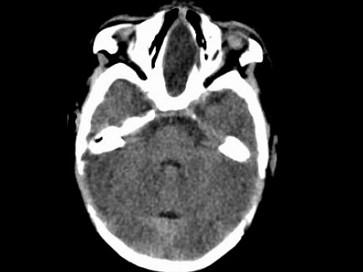

问题 两个月女婴,口咽部有一肿块,行CT检查如图,请选择最可能的诊断 ( )

选项 A、前脑无裂畸形 B、Dandy-Walker综合征 C、胼胝体发育不全 D、透明隔囊肿 E、脑积水

答案 C